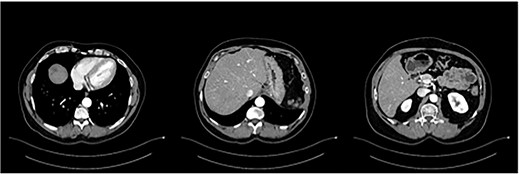

The postoperative course was uneventful and the patient was discharged after 7 days, followed by TACE of the right lobe 3 weeks after surgery. After 6 weeks, the patient received his first dose of the systematic chemotherapy with FOLFIRINOX. A follow-up CT scan confirmed that all remaining LMs in the right lobe had significantly decreased in size or vanished (Fig. 2). Tumor markers (CA19-9 and CEA) decreased continuously to normal levels (Figs. 3 and 4).

Status post-multimodal therapy with significant lesional downsizing or complete vanishing of cancerous lesions.